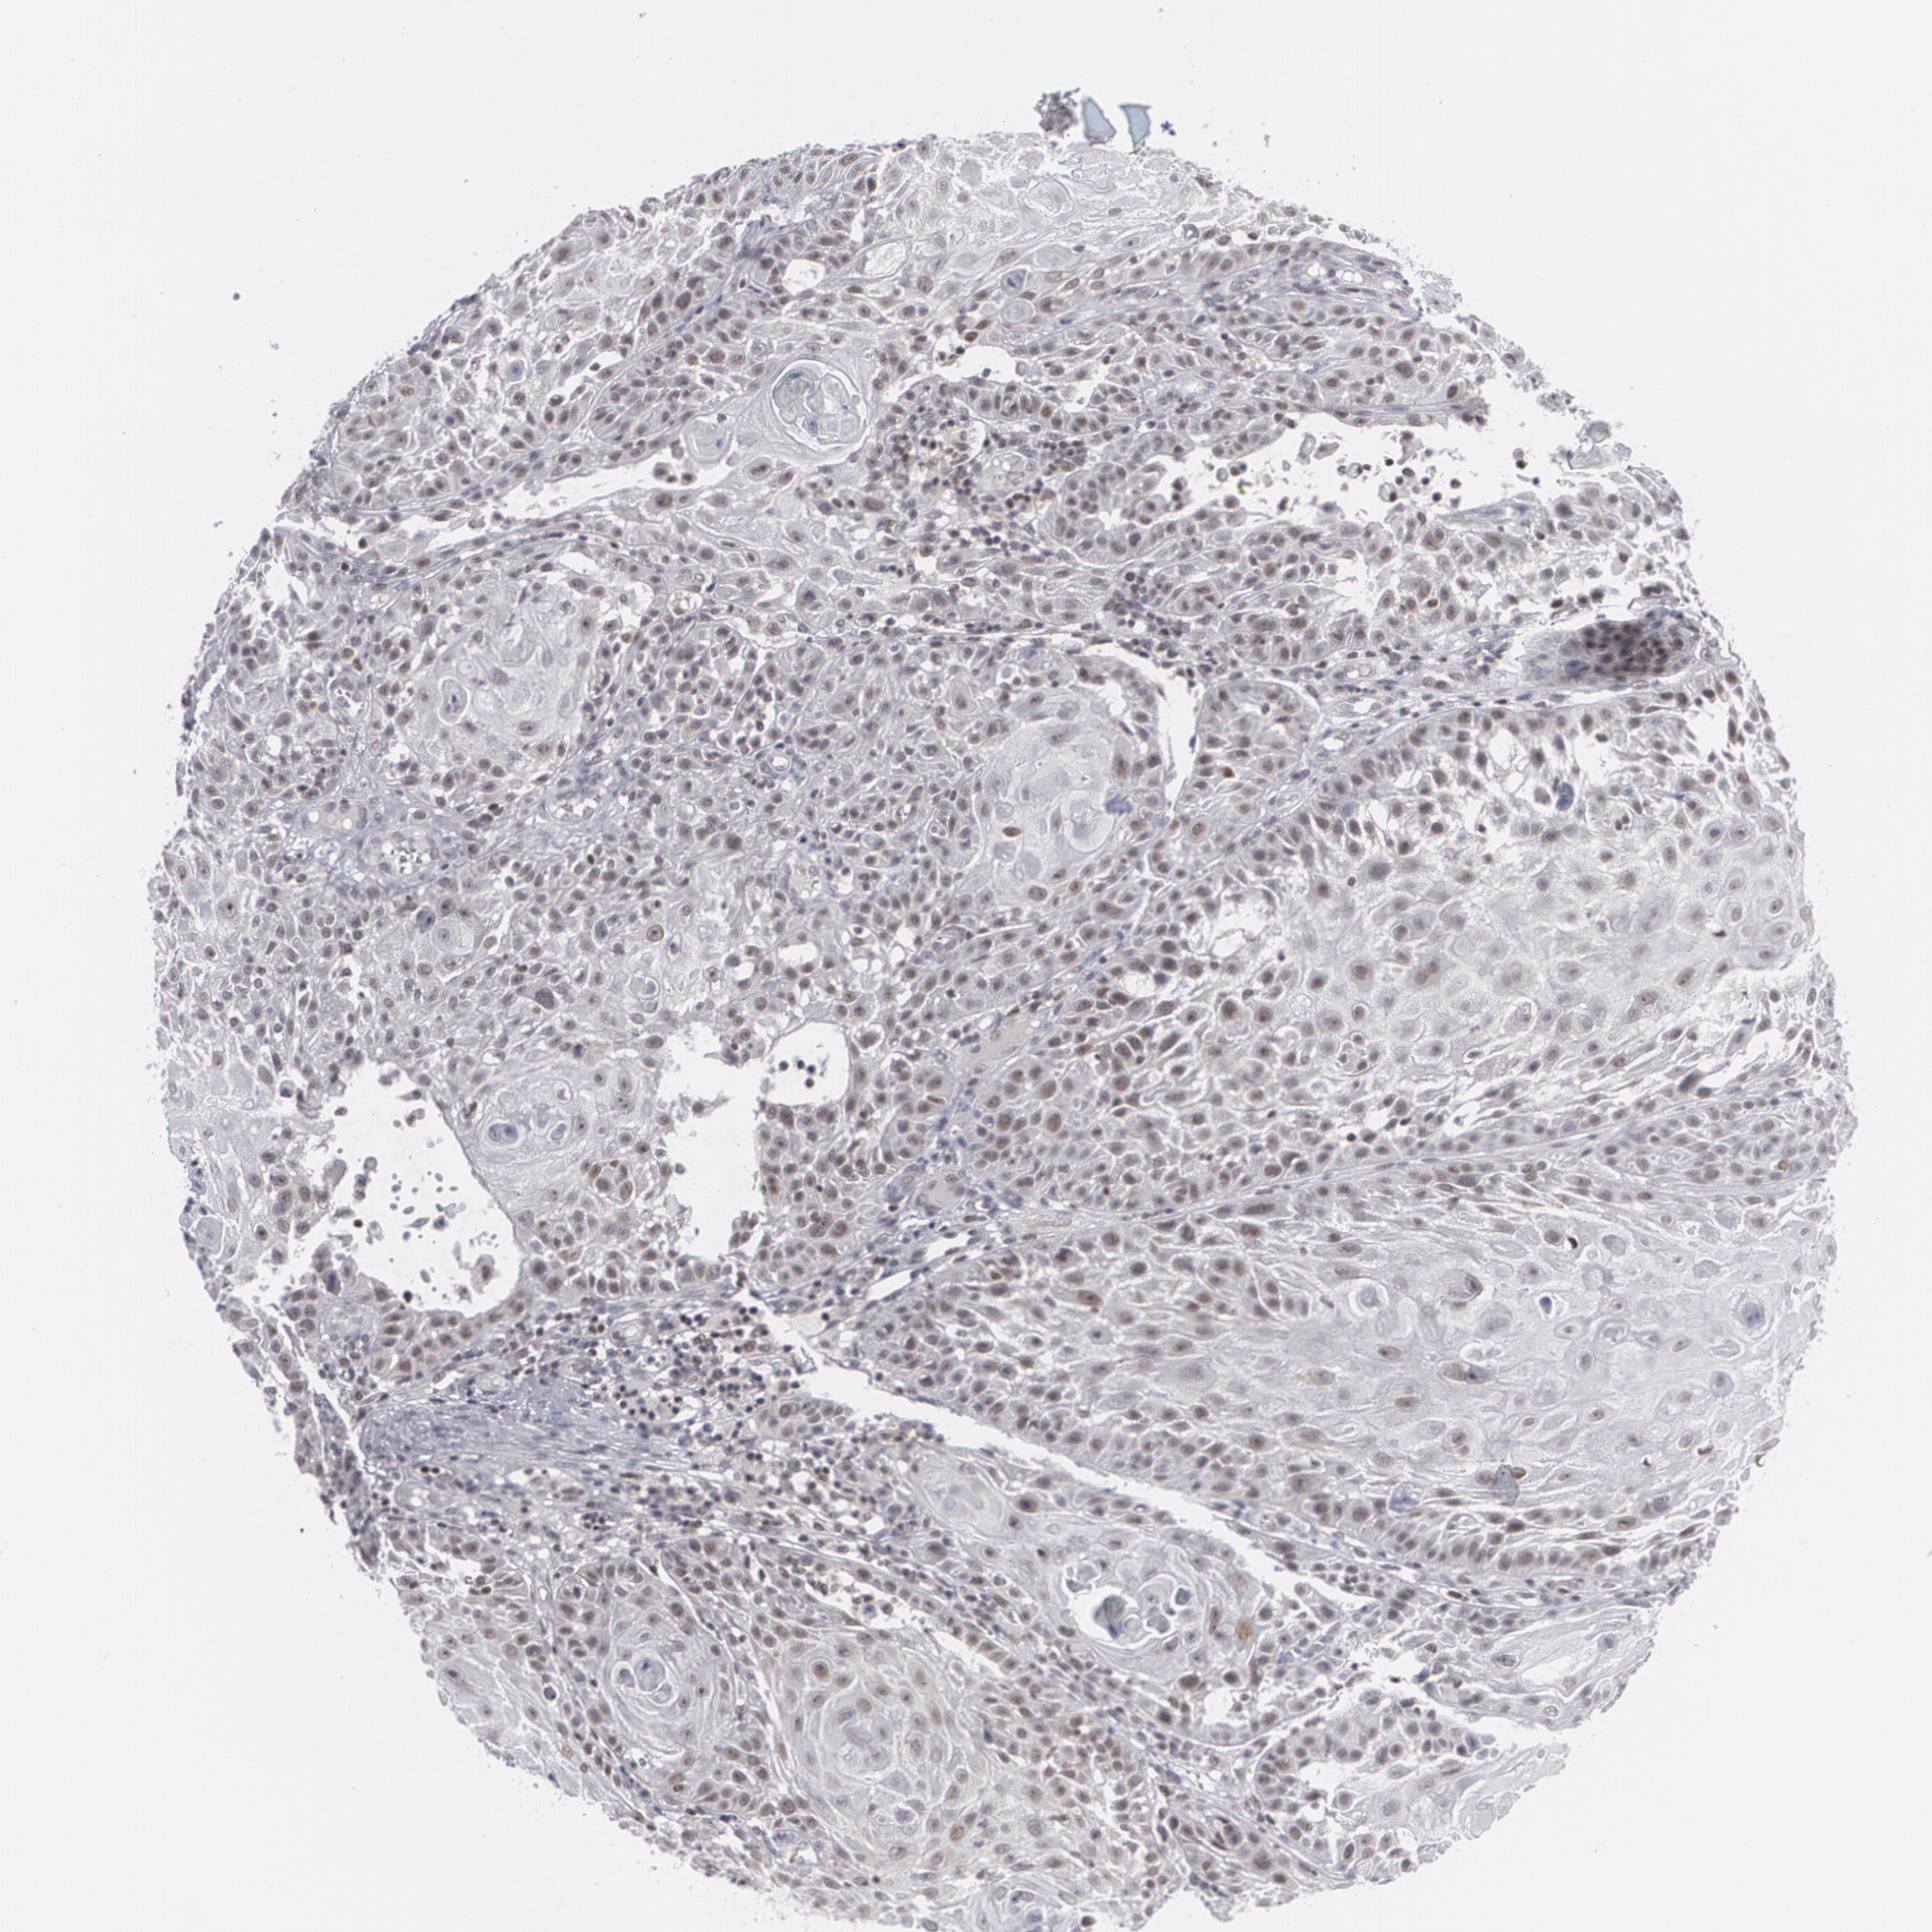

SKIN CANCER - Protein expressioni

A mouse-over function shows sample information and annotation data. Click on an image to view it in a full screen mode. Samples can be filtered based on level of antibody staining by selecting one or several of the following categories: high, medium, low and not detected. The assay and annotation is described here.

Antibody stainingi

Antibody staining in the annotated cell types in the current human tissue is reported as not detected, low, medium, or high, based on conventional immunohistochemistry profiling in selected tissues. This score is based on the combination of the staining intensity and fraction of stained cells.

Each image is clickable and will lead to virtual microscopy that enables deeper exploration of all samples and also displays staining intensity scores, fraction scores and subcellular localization as well as patient and tissue information for each sample.

Antibody HPA008455

Staining

High

Medium

Low

Not detected

Intensity

Strong

Moderate

Weak

Negative

Quantity

>75%

75%-25%

<25%

None

Location

Nuclear

Cytoplasmic/membranous

Cytoplasmic/membranous,nuclear

Squamous cell carcinoma, NOS

Squamous cell carcinoma, metastatic, NOS

Basal cell carcinoma